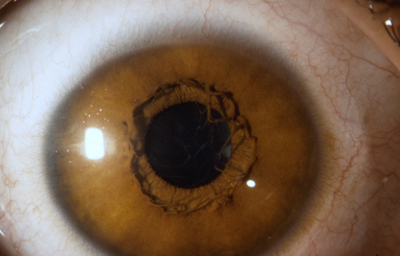

Diastasis: Significa la presencia de agujeros en la raíz del Iris parecidos a una Iridodiálisis

Diastasis del Iris: en un caso de Atrofia Esencial del Iris (Síndrome ICE)

Archivo Fotográfico Dr. Francisco Barraquer